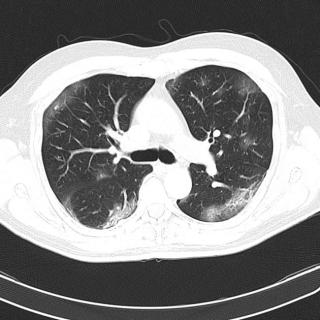

При подозрении на коронавирус могут назначить сделать КТ легких. Стоит сразу сказать, что КТ при COVID-19 проводится не в поточном порядке. Томографию целесообразно применять в ситуации, когда заболевание развивается с осложнениями в виде воспаления легких. Легкая форма коронавируса обычно проходит без признаков пневмонии, и делать компьютерную томографию при таком течении болезни не целесообразно.